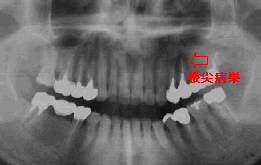

初診時 パノラマ 初診時 パノラマ

|45部に隣接面カリエス存在、それ以外異常なし

左側上顎洞部が白濁

清掃状態は不良で、全体にプラークや縁上歯石の沈着が認められる。|67の 咬合痛を訴え、打診痛(+)ではあるが、レントゲン診査では歯根膜炎や根尖病巣様の像は 認められない。また、|45隣接面にカリエスが存在するが、同歯牙には臨床症状は 存在しない。

レントゲン上、左側上顎洞の白濁が認められる。

歯石沈着に伴う歯肉炎による可能性もあるので、全体の歯石除去を行い、|45部 歯髄炎の有無確認を含めてカリエス治療を施行。歯科的には問題がないことを確かめた上で、 上顎洞炎(副鼻腔炎)の疑いで耳鼻科を紹介。

1週間後、“副鼻腔炎”の診断にて処置を行った結果、症状は軽快したとのことであった。

“走ると響く”という訴えに対しては、当該歯の根尖病巣が原因であることが多い。 本症例では、根管治療の形跡が全くなく、他に疑うべき疾患が存在しなかった上、歯科用 レントゲンにも異常が認められたので、容易に上顎洞炎の診断がついた。